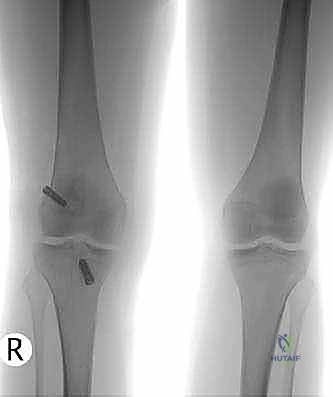

3. Routine radiographs, including weight-bearing anteroposterior and lateral views as well as patellar views, should be performed. In the revision setting, these images allow for critical assesment of previous tunnel placement and assesment for possible bone loss at previous tunnels, which may require further evaluation and treatment.

1. Metallic fixation devices make previous tunnel placement easy to identify, but bioabsorbable screws and other types of fixation also can be evaluated for tunnel placement on these images (

FIG 1

).

FIG 1 • A,B. Anterior cruciate ligament (ACL) reconstruction performed with an EndoButton (Smith & Nephew, Andover, MA) on the femur and staple fixation of the graft on the tibia. C,D. Anterior placement of the femoral tunnel in this primary ACL reconstruction performed with a two-incision technique. A B C